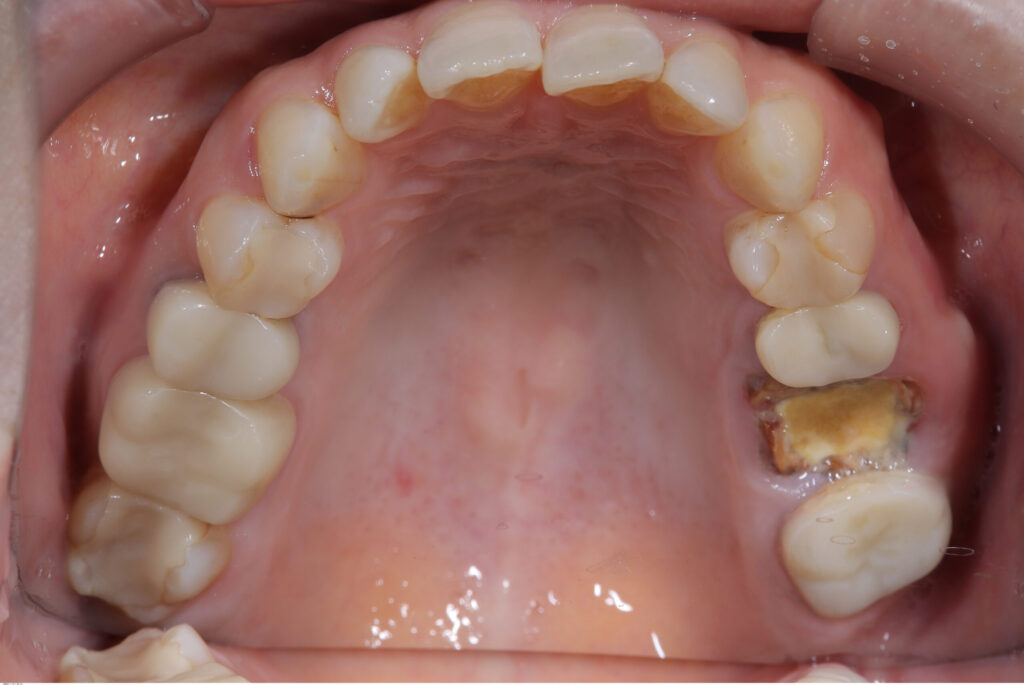

今回ご紹介させていただく症例の患者さまは

上顎の奥歯に痛みを感じ来院されました。

診査の結果、歯の大部分が崩壊し、

深い虫歯が歯ぐきの下まで進行している状態でした。

一見すると抜歯が妥当と考えられるケースでしたが、

歯根と周囲の骨の状態を精密に評価した結果、

保存可能と判断しました。